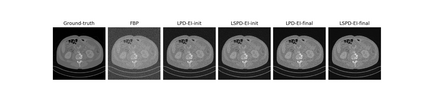

We propose a new type of efficient deep-unrolling networks for solving imaging inverse problems. Conventional deep-unrolling methods require full forward operator and its adjoint across each layer, and hence can be significantly more expensive computationally as compared with other end-to-end methods that are based on post-processing of model-based reconstructions, especially for 3D image reconstruction tasks. We develop a stochastic (ordered-subsets) variant of the classical learned primal-dual (LPD), which is a state-of-the-art unrolling network for tomographic image reconstruction. The proposed learned stochastic primal-dual (LSPD) network only uses subsets of the forward and adjoint operators and offers considerable computational efficiency. We provide theoretical analysis of a special case of our LSPD framework, suggesting that it has the potential to achieve image reconstruction quality competitive with the full-batch LPD while requiring only a fraction of the computation. The numerical results for two different X-ray computed tomography (CT) imaging tasks (namely, low-dose and sparse-view CT) corroborate this theoretical finding, demonstrating the promise of LSPD networks for large-scale imaging problems.